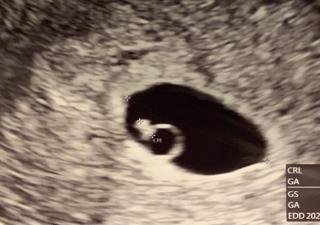

5w5dで2ミリの赤ちゃんに会えました。 心拍もピコピコと確認ができて感動。 次は1週間後なので今より大きく元気に成長していますように‼︎ 週数は6w1dに修正されました(◡̈)

詳しい説明はありませんでしたが、先生からは週数的にもちゃんと成長してるので大丈夫、とのことで一安心。 しかし帰宅後、もらったエコー写真と、第一子の同時期のエコー写真を見比べると形も全然違うので不安になりました。次回二週間後の検診まで待ち遠しいです。